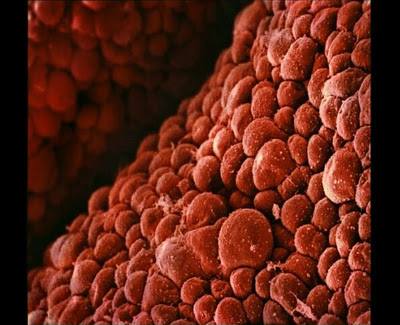

Սաղմի սրտի բջիջները